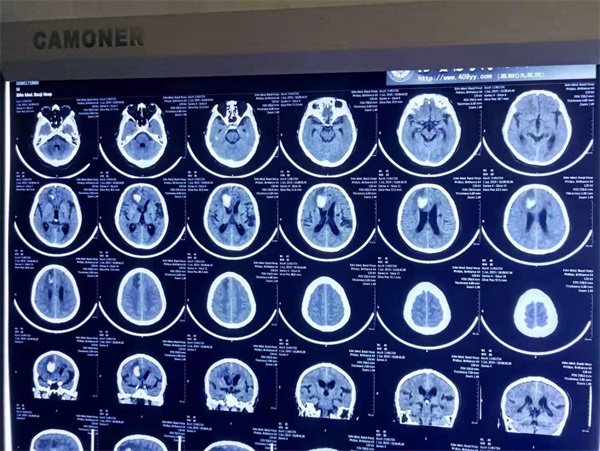

颅内动脉瘤在人群中发病率为8%左右,大多为中老年人群,俗称脑动脉瘤。其不是真正意义上的“肿瘤”,多为动脉血管壁上的异常膨出,好比自行车内胎鼓了个包,平时骑行没问题,一旦载人或者路面颠簸就会破口导致爆胎。脑动脉瘤从外形上看就好像动脉上长出了一个“瘤子”,被比喻为颅内“不定时炸弹”,一旦破裂会造成大出血危及生命,死亡率非常高。近日,附属宝鸡医院神经外科团队成功开展一例颅内动脉瘤夹闭术,使患者转危为安...